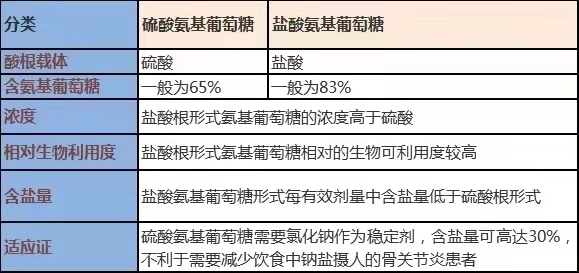

浓盐酸氨基红提葡萄糖注射液和酸洗氨基红提糖的区分

根治体验上看,两者之间没啥的不同于。但鉴于产品性,硫酸钠氨基红萄葡糖水与酸洗氨基红萄葡糖水有效氨糖的含量较前的不同。

不论什么氢氧化钠氨基草莓糖或许是硫酸氨基草莓糖,在结肠都以氨基草莓糖原形吸取。